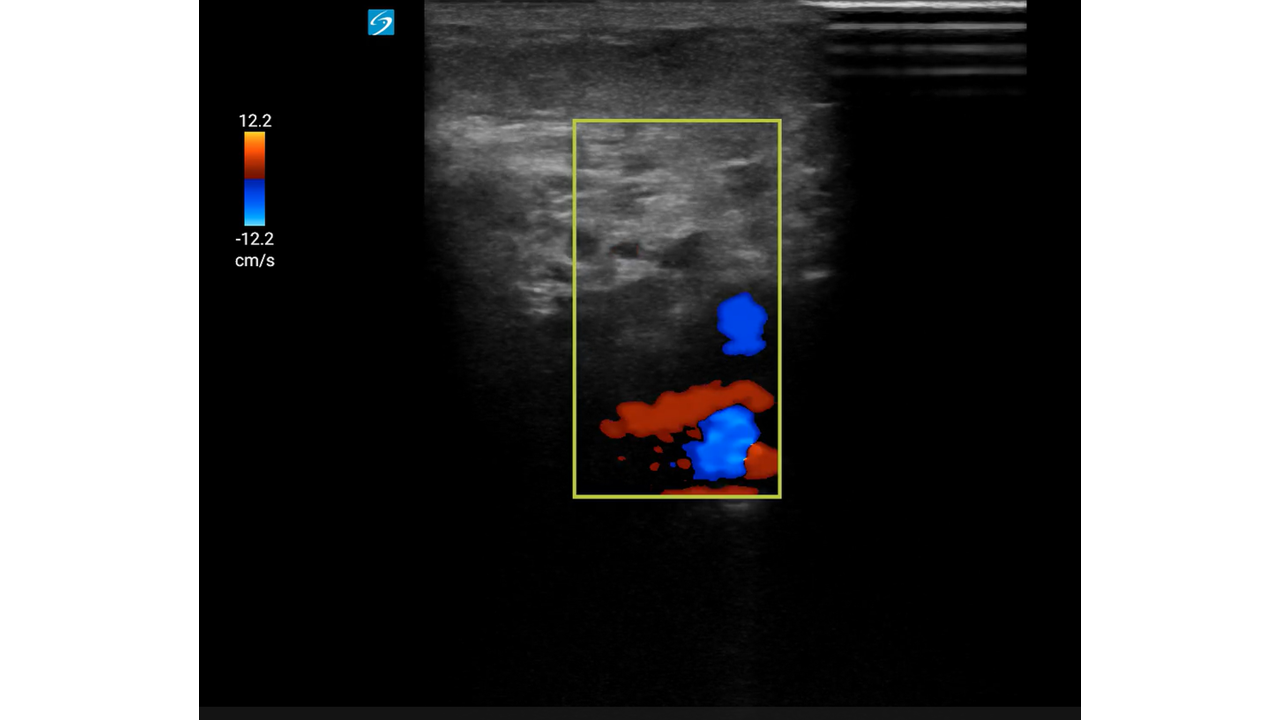

Mujer de 93 años con: fibrilación auricular, enfermedad renal crónica y antecedentes de hemorragias digestivas por las cuales se le había suspendido la anticoagulación oral meses antes.

Motivo de consulta: Dolor súbito, frialdad y pérdida de sensibilidad en la extremidad inferior derecha (EID), con mejoría parcial durante el traslado.

Con mejoría del dolor y pulso poplíteo dudoso, se duda del diagnóstico.

Con sospecha inicial de Isquemia Arterial Aguda (IAA), la mejoría clínica hace dudar abriendo el diagnóstico diferencial a una posible radiculopatía.

Con sospecha clínica de IAA, la ecografía vascular es clave para confirmar el diagnóstico. Su curva de aprendizaje es rápida, se puede utilizar en cualquier punto del sistema y permite derivar al paciente a un centro útil evitando demoras potencialmente fatales.